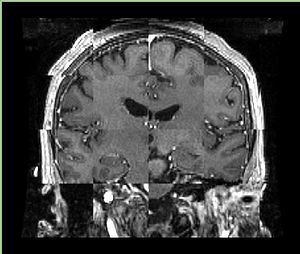

• Checkerboard appearance of unregistered images for the representative data of interest

• Case03